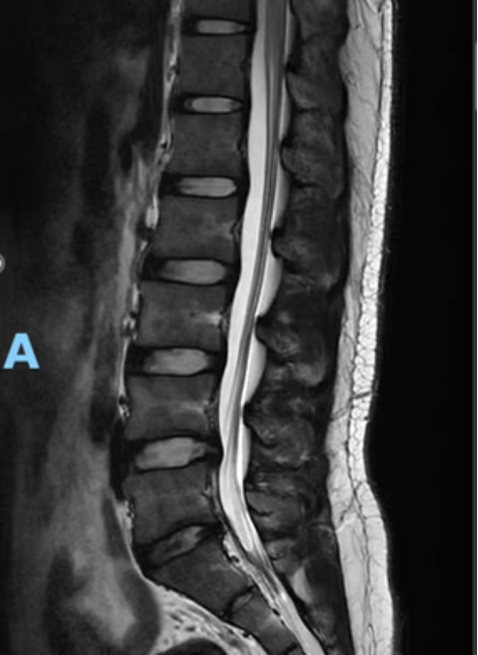

L4–5和L5–S1椎间盘轻度突出,伴纤维环裂隙,轻度压迫L5双侧及S1左侧神经根 -

L4–5轻度双侧小关节关节炎 注:影像常见“假阳性”,许多无症状者也有椎间盘突出或退变表现,这些变化可能只是老化过程的一部分。